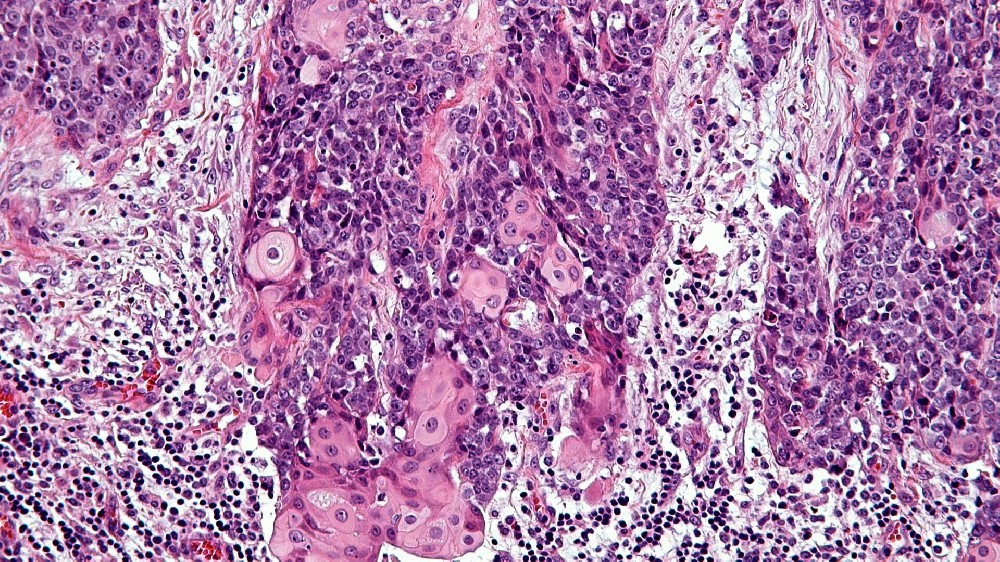

中線管癌 (NUT 癌症)是一種極為罕見但具侵略性的癌症,特徵為特定的基因突變。這種惡性腫瘤通常發生在身體的中線結構,如肺、縱膈、鼻腔或唾液腺,其特徵是位於 15 號染色體的睪丸核蛋白 (NUTM1) 基因重排。由此產生的基因改變會促進異常的細胞增殖和快速的腫瘤生長。

近年來,由 James P. Allison 教授和 Gregg Semenza 博士等知名諾貝爾獎得主所贊同的突破性研究,已闡明 NUT Carcinoma 的分子結構。這種癌症的表現主要是由於融合的染色體易位所致。 NUTM1 基因與 BRD4 或 BRD3 等基因,造成快速且無法控制的細胞分裂。

中線縱膈癌 (Midline Tract Carcinoma) 主要是由涉及 NUTM1 基因的特定基因易位所引起。與 BRCA1/BRCA2 基因突變相關的乳癌或 EGFR 基因突變相關的肺癌不同,NUT Carcinoma 特別涉及融合基因異常 (尤其是 NUT-BRD4)。雖然大多數患者不會遺傳這些突變,但已觀察到罕見的家族聚集,顯示個別病例有遺傳傾向。